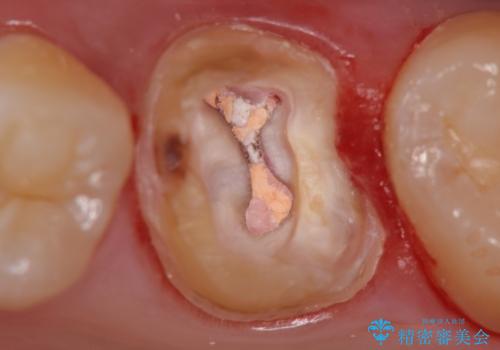

被せ物を除去し、根管治療を進めた後に新しい被せ物を装着していきます。

本来は歯茎をしっかりと下げる外科処置が適応となるケースでしたが、ご希望がなかったため最小限の侵襲に抑えて治療を行いました。

根の中を洗浄し、結果的に適合の良い被せ物をセットすることができました。